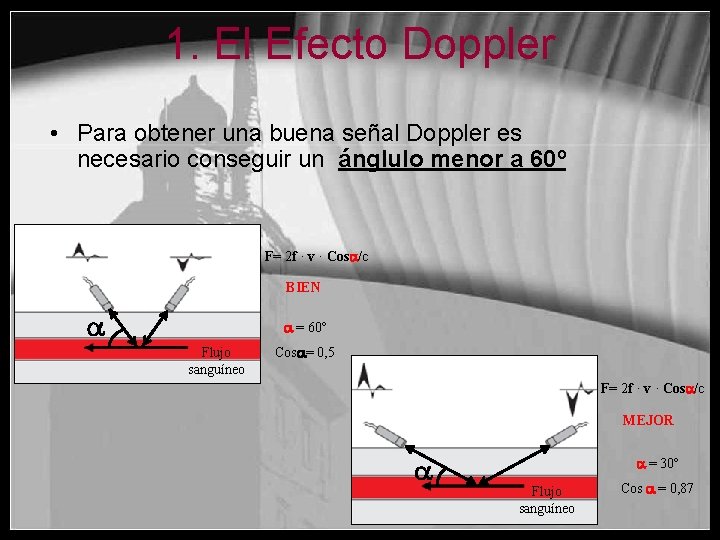

1. El Efecto Doppler • Para obtener una buena señal Doppler es necesario conseguir un ánglulo menor a 60º F= 2 f · v · Cos /c BIEN = 60º Flujo sanguíneo Cos = 0, 5 F= 2 f · v · Cos /c MEJOR = 30º Flujo sanguíneo Cos = 0, 87